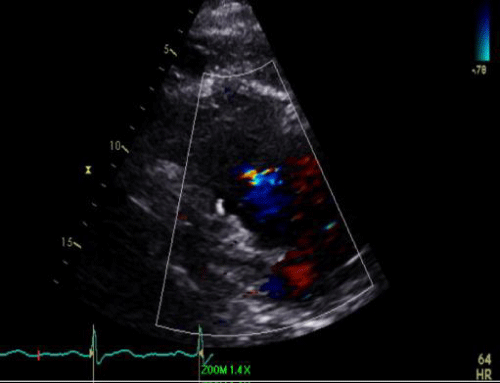

Trans Esophageal Echocardiogram (TEE) esophageal view demonstrating Mitral Valve (MV) annulus dilation

With severe, central (functional) Mitral Regurgitation (MR) with color flow